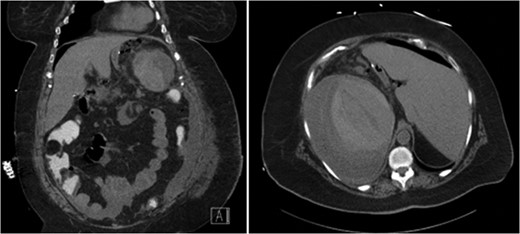

Unfortunately, she presented once more, 20 days after the initial operation with symptomatic hypotension and complaints of severe left upper quadrant pain after a fall in her home. CT scan demonstrated extravasation of intravenous contrast into the peritoneum as well as free intra-peritoneal air (Fig. 2). Given her hemodynamic instability and splenic injury, she was immediately taken to the operating room and underwent an open splenectomy. At the time of splenectomy, only old clotted blood was noted without evidence of purulent fluid or infection. She had a prolonged hospital course but was eventually discharged to a rehabilitation facility.

CT abdomen demonstrating extravasation of contrast and free intra-peritoneal air, with the absence of subcapsular air.